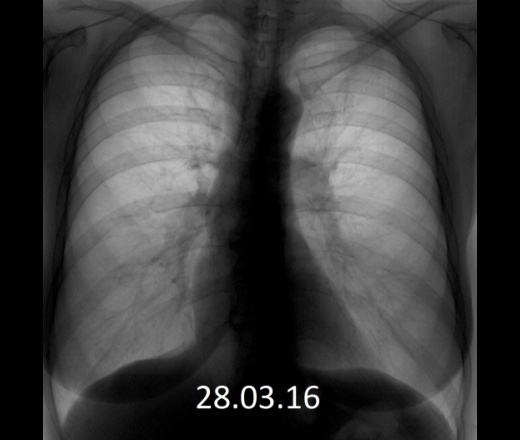

ΠΠΎΠΏΡΠΎΡ: ΠΌΠΎΠΆΠ½ΠΎ Π»ΠΈ ΠΏΠΎ ΡΠ»ΡΠΎΡΠΎΠ³ΡΠ°ΡΠΈΠΈ ΠΎΠΏΡΠ΅Π΄Π΅Π»ΠΈΡΡ, ΡΡΠΎ ΡΠ΅Π»ΠΎΠ²Π΅ΠΊ Π½Π°ΡΠ°Π» ΠΊΡΡΠΈΡΡ? ΠΡΠ²Π΅Ρ: Π½Π΅Ρ, Π½Π΅Π»ΡΠ·Ρ.

ΠΠΎΠΆΠ½ΠΎ Π»ΠΈ ΠΏΠΎ ΡΠ»ΡΠΎΡΠΎΠ³ΡΠ°ΡΠΈΠΈ ΠΏΠΎΠ½ΡΡΡ, ΡΡΠΎ ΡΠ΅Π»ΠΎΠ²Π΅ΠΊ ΠΊΡΡΠΈΡ

ΠΡΠ²Π΅Ρ Π½Π° ΡΡΠΎΡ Π²ΠΎΠΏΡΠΎΡ Π·Π°Π²ΠΈΡΠΈΡ ΠΎΡ ΡΡΠ°ΠΆΠ° ΠΊΡΡΠ΅Π½ΠΈΡ: ΡΠ΅ΠΌ Π΄ΠΎΠ»ΡΡΠ΅ ΠΈ Π°ΠΊΡΠΈΠ²Π½Π΅Π΅ ΡΠ΅Π»ΠΎΠ²Π΅ΠΊ ΠΊΡΡΠΈΡ, ΡΠ΅ΠΌ Π·Π°ΠΌΠ΅ΡΠ½Π΅Π΅ ΡΡΠ°Π½ΠΎΠ²ΠΈΡΡΡ Π½Π° ΡΠ½ΠΈΠΌΠΊΠ°Ρ ΡΡΠΎΠ½, Π½Π°Π½Π΅ΡΠ΅Π½Π½ΡΠΉ Π΅Π³ΠΎ Π·Π΄ΠΎΡΠΎΠ²ΡΡ. ΠΠ°Π»Π΅Π½ΡΠΊΠΈΠΉ ΡΡΠ°ΠΆ ΠΈ ΡΠ΅Π΄ΠΊΠΈΠ΅ ΠΏΠ΅ΡΠ΅ΠΊΡΡΡ Π½Π° ΡΠ½ΠΈΠΌΠΊΠ°Ρ Π·Π°ΠΌΠ΅ΡΠ½Ρ Π½Π΅ Π±ΡΠ΄ΡΡ, ΠΎΠ΄Π½Π°ΠΊΠΎ ΠΊΠΎΠ³Π΄Π° ΠΏΠΎΡΠ°ΠΆΠ΅Π½ΠΈΠ΅ Π»Π΅Π³ΠΊΠΈΡ Π΄ΠΎΡΡΠΈΠ³Π½Π΅Ρ ΠΏΠ°ΡΠΎΠ»ΠΎΠ³ΠΈΡΠ΅ΡΠΊΠΎΠ³ΠΎ Π·Π½Π°ΡΠ΅Π½ΠΈΡ ΠΈΠ»ΠΈ ΠΏΠΎΡΠ²ΡΡΡΡ Π·Π°ΠΌΠ΅ΡΠ½ΡΠ΅ ΠΈΠ·ΠΌΠ΅Π½Π΅Π½ΠΈΡ Π² ΡΠ°Π·ΠΌΠ΅ΡΠ°Ρ ΡΠ΅ΡΠ΄Π΅ΡΠ½ΠΎΠΉ ΠΌΡΡΡΡ, ΡΠΎ ΠΈ ΡΠ°ΠΊΡ ΠΊΡΡΠ΅Π½ΠΈΡ Π±ΡΠ΄Π΅Ρ ΡΠΆΠ΅ Π½Π΅ ΡΠΊΡΡΡΡ.

ΠΡΠΌ Π½Π°Π½ΠΎΡΠΈΡ ΡΠ΅ΡΡΠ΅Π·Π½ΡΠΉ Π΄Π΅ΡΡΡΡΠΊΡΠΈΠ²Π½ΡΠΉ Π²ΡΠ΅Π΄ ΠΎΡΠ³Π°Π½ΠΈΠ·ΠΌΡ, ΠΏΠΎΡΡΠΎΠΌΡ ΡΡΠ·ΠΈΠ²ΡΠΈΠ΅ΡΡ Π±ΡΠΎΠ½Ρ ΠΈ Π² ΡΠΎΠ²ΠΎΠΊΡΠΏΠ½ΠΎΡΡΠΈ Ρ Π΄ΡΡΠ³ΠΈΠΌΠΈ ΡΠΈΠΌΠΏΡΠΎΠΌΠ°ΠΌΠΈ Π»Π΅Π³ΠΊΠΎ ΠΏΠΎΠ΄ΡΠΊΠ°ΠΆΡΡ Π²ΡΠ°ΡΡ ΠΎ ΡΠ΅Π³ΡΠ»ΡΡΠ½ΠΎΠΌ ΠΊΡΡΠ΅Π½ΠΈΠΈ ΠΏΠ°ΡΠΈΠ΅Π½ΡΠ°.

ΠΡΠ΄Π΅Ρ Π»ΠΈ Π²ΠΈΠ΄Π½Π° Π²ΡΠΊΡΡΠ΅Π½Π½Π°Ρ ΠΏΠ΅ΡΠ΅Π΄ ΡΠ»ΡΠΎΡΠΎΠ³ΡΠ°ΡΠΈΠ΅ΠΉ ΡΠΈΠ³Π°ΡΠ΅ΡΠ°

ΠΠ΅ ΠΈΠΌΠ΅Π΅Ρ Π·Π½Π°ΡΠ΅Π½ΠΈΡ, ΠΏΠΎΠΊΡΡΠΈΠ» ΡΠ΅Π»ΠΎΠ²Π΅ΠΊ ΠΏΡΡΠΌΠΎ ΠΏΠ΅ΡΠ΅Π΄ ΡΠ΅ΠΌ, ΠΊΠ°ΠΊ Π·Π°ΠΉΡΠΈ ΠΊ ΡΠ΅Π½ΡΠ³Π΅Π½ΠΎΠ»ΠΎΠ³Ρ, ΠΈΠ»ΠΈ Π²ΠΎΠ·Π΄Π΅ΡΠΆΠΈΠ²Π°Π»ΡΡ Π½Π΅ΡΠΊΠΎΠ»ΡΠΊΠΎ Π΄Π½Π΅ΠΉ, ΠΎΠΏΠ°ΡΠ°ΡΡΡ Π·Π° ΡΠ½ΠΈΠΌΠΊΠΈ.

ΠΠ½Π΅ΡΠ½ΠΈΠΉ Π²ΠΈΠ΄ Π·Π΄ΠΎΡΠΎΠ²ΡΡ ΠΈ ΠΏΠΎΡΠ°ΠΆΠ΅Π½Π½ΡΡ Π»Π΅Π³ΠΊΠΈΡ

ΠΠ΄ΠΎΡΠΎΠ²ΡΠ΅ Π»Π΅Π³ΠΊΠΈΠ΅ ΡΠ΅Π»ΠΎΠ²Π΅ΠΊΠ°, ΠΊΠΎΡΠΎΡΡΠΉ Π½Π΅ ΠΊΡΡΠΈΡ, ΠΈΠΌΠ΅ΡΡ ΡΠΎΠ·ΠΎΠ²ΡΠΉ ΠΈΠ»ΠΈ ΠΊΡΠ°ΡΠ½ΡΠΉ ΡΠ²Π΅Ρ, Π² ΡΠΎ Π²ΡΠ΅ΠΌΡ ΠΊΠ°ΠΊ Π»Π΅Π³ΠΊΠΈΠ΅ ΠΊΡΡΡΡΠ΅Π³ΠΎ ΡΠ΅Π»ΠΎΠ²Π΅ΠΊΠ° ΠΌΠΎΠ³ΡΡ ΡΠΎ Π²ΡΠ΅ΠΌΠ΅Π½Π΅ΠΌ ΡΡΠ°ΡΡ ΡΠ΅ΡΠ½ΡΠΌΠΈ ΠΈΠ»ΠΈ ΡΠ΅ΡΡΠΌΠΈ (Π² Π·Π°Π²ΠΈΡΠΈΠΌΠΎΡΡΠΈ ΠΎΡ ΡΠΎΠ³ΠΎ, Π½Π°ΡΠΊΠΎΠ»ΡΠΊΠΎ Π΄Π°Π²Π½ΠΎ ΠΈ ΡΠ°ΡΡΠΎ ΠΎΠ½ ΠΊΡΡΠΈΡ). ΠΡΠΈΡΠΈΠ½ΠΎΠΉ ΠΎΠ±Π΅ΡΡΠ²Π΅ΡΠΈΠ²Π°Π½ΠΈΡ ΡΠ²Π»ΡΠ΅ΡΡΡ ΡΠΌΠΎΠ»Π° Ρ ΡΠ΅ΡΠ½ΡΠΌ ΠΏΠΈΠ³ΠΌΠ΅Π½ΡΠΎΠΌ (ΡΠ²Π΅ΡΠ΄ΡΠ΅ ΡΠ°ΡΡΠΈΡΡ, ΠΎΠ±ΡΠ°Π·ΡΡΡΠΈΠ΅ΡΡ ΠΏΡΠΈ ΡΠΆΠΈΠ³Π°Π½ΠΈΠΈ ΡΠ°Π±Π°ΠΊΠ°), ΠΊΠΎΡΠΎΡΡΠ΅ Π²Π΄ΡΡ Π°ΡΡΡΡ, ΠΊΠΎΠ³Π΄Π° ΡΠ΅Π»ΠΎΠ²Π΅ΠΊ Π·Π°ΡΡΠ³ΠΈΠ²Π°Π΅ΡΡΡ ΡΠΈΠ³Π°ΡΠ΅ΡΠΎΠΉ. ΠΠ»ΠΈΡΠ½ΠΈΠ΅ ΡΠΈΠ³Π°ΡΠ΅Ρ Π½Π° ΡΠΎΡΡΠ΄Ρ Π½Π°ΠΌΠ½ΠΎΠ³ΠΎ ΡΠΈΠ»ΡΠ½Π΅Π΅, ΡΠ΅ΠΌ ΠΌΠΎΠΆΠ΅Ρ ΠΏΠΎΠΊΠ°Π·Π°ΡΡΡΡ Π½Π° ΠΏΠ΅ΡΠ²ΡΠΉ Π²Π·Π³Π»ΡΠ΄.